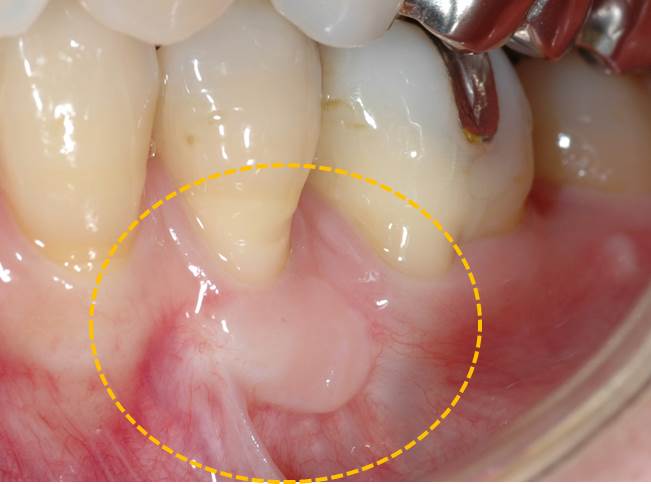

術前写真です。

ヨウド(J)で歯肉を染めたところです。歯肉が黒く染まっている部分が歯槽粘膜といい、この部分が歯の根元の部分まで覆われているために歯肉退縮が起こってしまうと考えられます。

上顎口蓋から歯肉を採取し、移植しました。

術後です。しっかりとした付着歯肉が獲得でき、安定しています。

術前術後の比較です。術前と術後では歯肉の厚み、幅が違うのが確認できます。露出した歯根部分に歯肉が被ってきました。